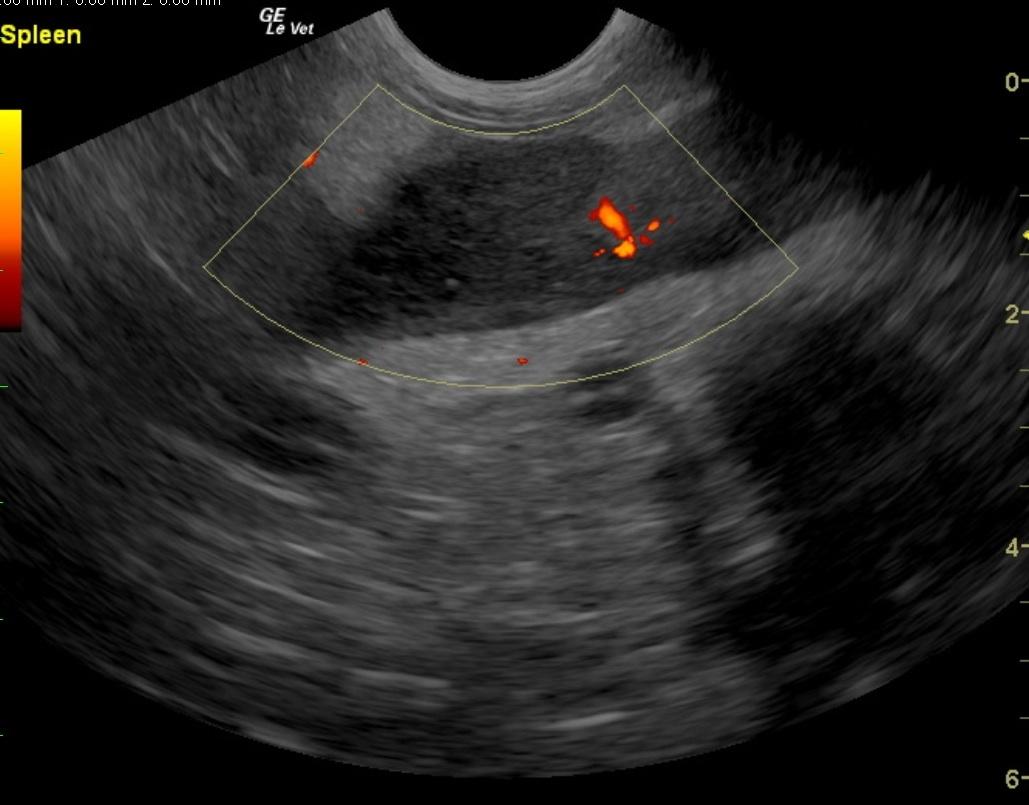

A 7-year-old FS Jack Russell Terrier with a history of regulated hypothyroidism, was presented for vomiting, lateral recumbency, and abdominal pain following ingestion of a ham bone. The owner also reported that the patient had been showing polyuria/polydipsia prior to the incident. On physical examination, the patient was laterally recumbent and very painful. CBC showed polycythemia and low band neutrophils. On blood chemistry, mildly elevated BUN, elevated creatinine, elevated ALP activity, elevated lipase, severely elevated ALT activity, and elevated cPLI were evident. A hemorrhagic diathesis was present on coagulation panel. Blood pressure was 145/80. The patient was treated with I.V. fluids, hetastarch, morphine/ketamine drip, fresh frozen plasma, antibiotics, and placed in an oxygen cage. On survey abdominal radiographs, bony fragments were evident in the gastrointestinal tract. The patient was sedated, given an enema, and a large piece of bone was produced. After 42 hours on therapy the patient developed dyspnea, which, on survey thoracic radiographs, was suggestive of fluid overload. Lasix was administered, which resulted in resolution of the dyspnea. Recheck blood chemistry showed hypoproteinemia, elevated ALP activity, hyperglycemia, improved azotemia, and normalization of cPLI. Physical examination, after 72 hours of supportive care, found the patient BAR and ambulatory, not interested in food, and still extremely painful upon palpation of the right mid-abdomen. Syringe feedings were started, which were well tolerated with no vomiting. However, the following morning the patient was less bright and more painful in the abdomen.